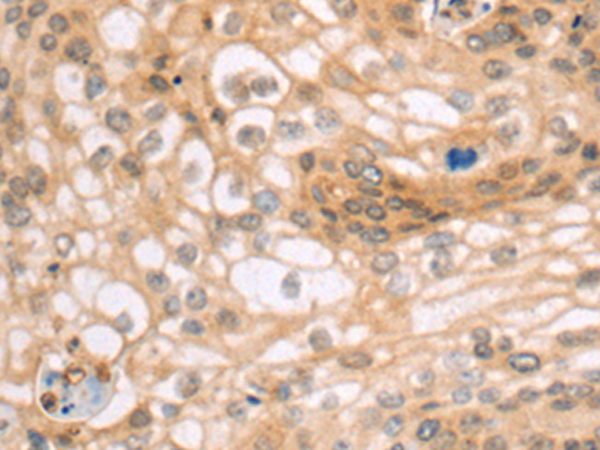

分类: 科研抗体货号: P08125别名: OX2R; MOX2R; CD200R; HCRTR2应用: IHC反应种属: Human